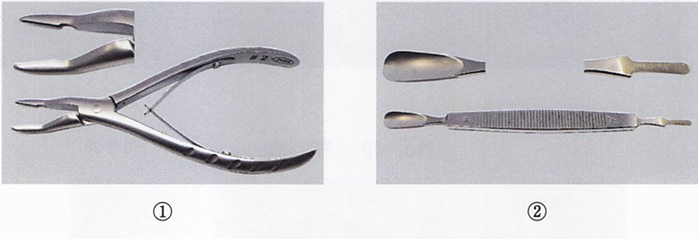

器具の写真を別に示す。 歯肉切除術に使用するのはどれか。2つ選べ。

a. ①

b. ②

c. ③

d. ④

解答を見る

a.d